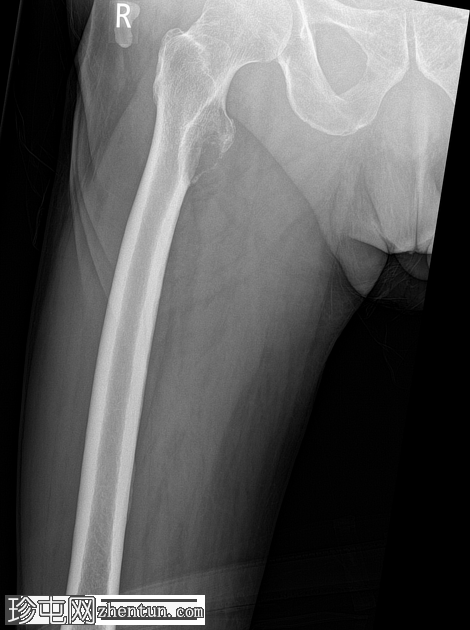

临床详情:

右髋部疼痛加剧,负重困难。已知甲状腺癌骨转移。

报告:

右股骨近端小转子水平处出现溶骨性病变,病变呈扩张性,并伴有皮质破坏。鉴于已知甲状腺恶性肿瘤伴骨转移病史,推测为转移性病变。无病理性骨折。

建议骨科/肿瘤科诊治。